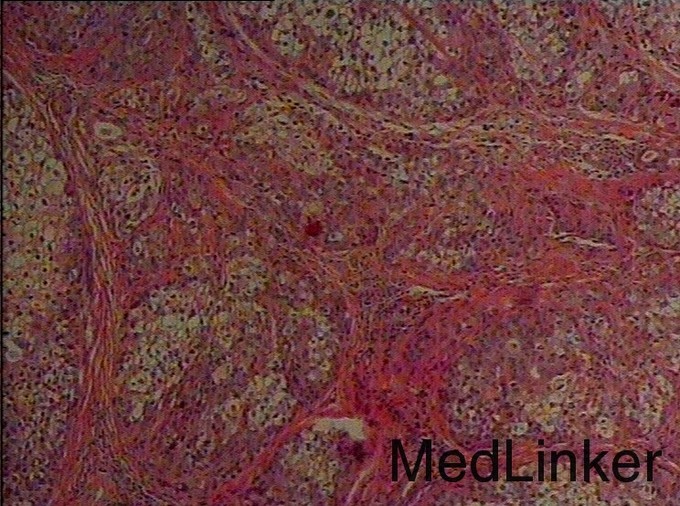

诊断:输尿管癌? 治疗:经术前准备,行右侧输尿管镜镜检+肿物活检术,手术顺利,术后病理示:高级别浸润性尿路上皮癌。与家属充分沟通及完善术前准备后,行腹腔镜下右肾、右输尿管癌根治性切除术,手术顺利,术后恢复较好,术后病理示:符合高级别浸润性尿路上皮癌。

讨论:输尿管恶性肿瘤多来源于输尿管上皮组织,以移行细胞癌最常见,移行细胞癌多呈乳头状生长,突入腔内,约1/3为多发性肿瘤。影像表现为输尿管、肾盂和肾盏不同程度扩张积水,并于输尿管梗阻端发现软组织肿块或腔内有充盈缺损,增强扫描轻中度强化,集合临床表现,多可作出诊断,不过应注意输尿管癌的多发性,勿漏诊!